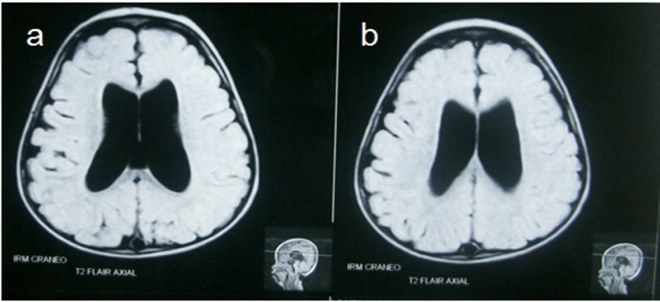

MRI head (FLAIR sequence; two axial planes)

of a young child with Dilated lateral ventricles are seen in the center of both images.